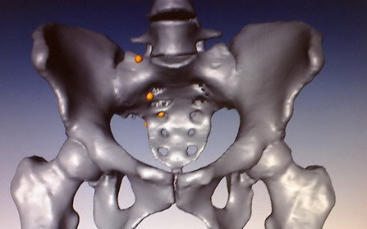

vermelden. Ich erinnert euch alle an die Bilder, die wir euch nach der Operation gezeigt haben. Hier ist es auf dem Foto noch einmal zu

sehen. Es ist ihr operativ das rechte Wadenbein aus dem Bein entfernt und als Stütze in das Becken eingesetzt worden, dort, wo vorher

die Beckenschaufel war. Das ist schon ein Meisterwerk ärztlicher Kunst gewesen. Und Gott hat Gelingen und Segen dazu gegeben. Die

Schmerzen, die Puschel in den letzten Tagen mehr hatte als sonst, rühren jetzt daher, dass der Knochen etwa an der Stelle, auf die der

Pfeil zeigt, richtiggehend durchgebrochen ist. Die Ärzte sprechen von einem Ermüdungsbruch. Der Knochen ist in der Substanz während

der Zeit der Chemo und der dadurch beabsichtigten Verhinderung der Neubildung von Zellen (Zielpunkt waren natürlich die

Krebszellen) zurückgegangen und ermüdet. Das große Problem ist, dass nun noch weniger Stabilität da ist und der Knochen erst wieder

Regenerierung ist weit grösser als der eventuelle Schaden. Dr. Tunn, der Arzt, der Puschel operiert hat, war nicht wirklich erstaunt oder

enttäuscht, dass der eingesetzte Knochen gebrochen ist. Für ihn kam es nicht wirklich überraschend. Der Knochen hat offensichtlich während der

lange Chemozeit einiges an Substanz verloren und war demzufolge auch brüchig geworden. Er ist nicht an einer “Nahtstelle” gebrochen, sondern

im Knochen selbst. Und das ist nun eher positiv. Denn Gott hat den Knochen die Fähigkeit mitgegeben, einen sogenannten Kallus auszubilden, also

eine Art Wulst, der hinüberwächst zum anderen gebrochenen Ende. Dadurch wird der Knochen sogar in einem größeren Bereich sogar stärker als

vorher. Und das sogar unter normalen Bewegungen. Da die nun natürlich nicht zu heftig sein dürfen, hat Puschel zwei Probleme damit: die

vermehrten Schmerzen und die verordnete Bettruhe für mindestens 6-8 Wochen. Allerdings darf sie “normale Verrichtungen” selbst machen.